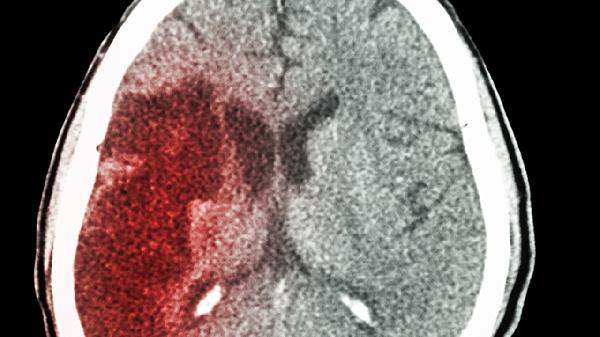

52岁大叔一月3次脑梗,医生痛心:这些警告信号别再忽视!

52岁的张先生怎么也没想到,短短30天内自己会三次被送进急诊室。第一次发病时他以为只是普通头晕,第二次还坚持去上班,直到第三次才意识到问题的严重性。这种“小中风”反复发作,其实是身体在拼命发送求.救信号。